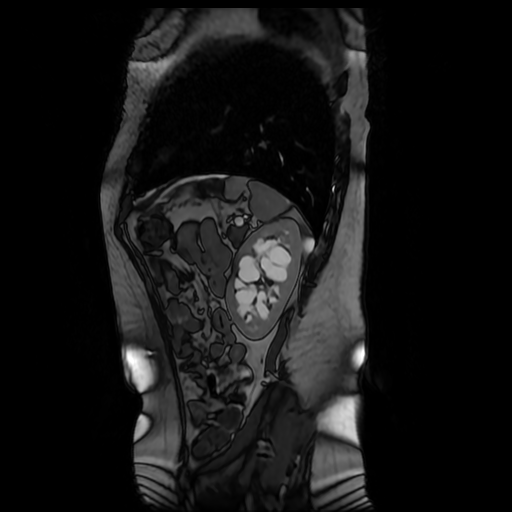

Los sistemas colectores del riñón derecho y del riñón izquierdo, muestran alteración de sus calices primarios y secundarios, mostrando dilatación, la pelvis renal y el uréter se observan de características normales lo que indica que no hay proceso obstructivo.

Se observa dilatación del sistema calicial sin proceso obstructivo compatible con una anormalidad del desarrollo de los sistemas colectores de ambos riñones, definiéndose como una “megacaliosis”